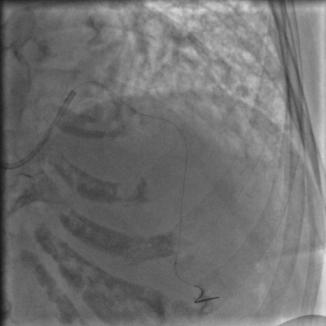

常规消毒、铺巾,再穿刺、放鞘管、送入造影导管、造影,一切顺利,造影结果如下:

图2

图3

图4

比我们想象中的要好,前降支中段闭塞,第一、第二对角支都还在,回旋支、右冠都还好,可以稍微松一口气。